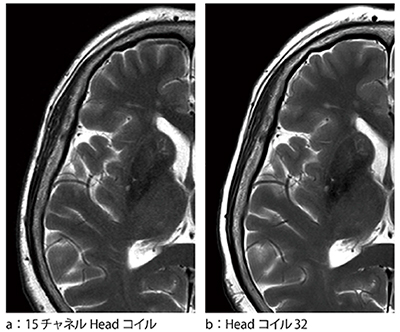

コイルエレメント数が増えたことにより,32チャネルコイルに最適化した撮像条件と15チャネルコイルにてほぼ同一の撮像時間で撮像した頭部画像例を図6に示す。図は拡大して提示しているが,32チャネルコイルでは画像SNRの改善によりノイズが低減し,空間分解能の向上も得られている。

図6 画像の比較(拡大画像)